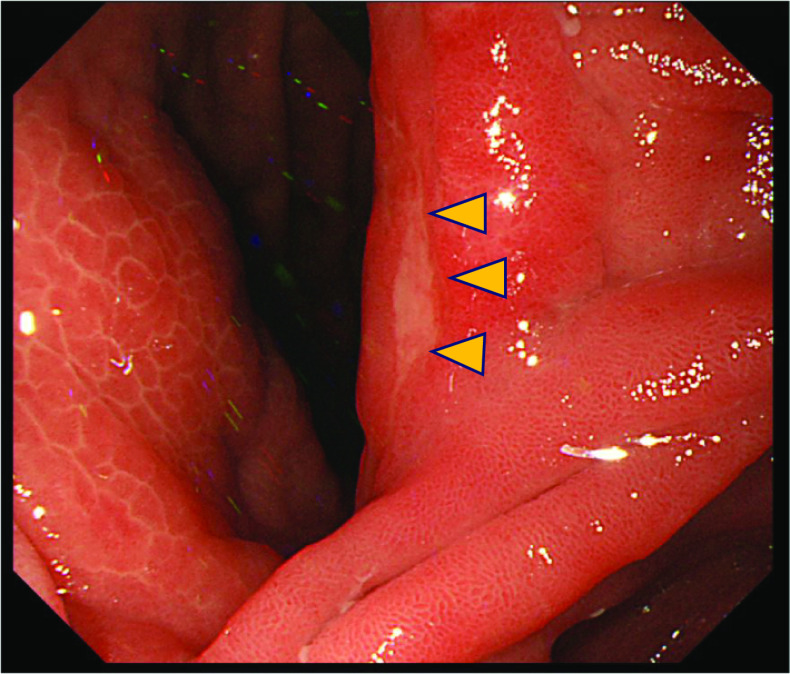

Case presentation: A 67-year-old man underwent a follow-up upper endoscopy 18 months after a partial gastrectomy for gastric cancer; an ulcerative lesion was found in the remnant stomach at the gastrojejunal anastomosis. A biopsy revealed gastric signet-ring cell carcinoma (SRCC). A full-body examination revealed no abnormalities other than gallstones in the gallbladder. With a diagnosis of residual gastric cancer (cT2N0M0 cStage I), the patient underwent open total gastrectomy and cholecystectomy. Macroscopic findings of the resected specimen revealed thickening of the gallbladder wall; however, no obvious neoplastic lesions were found on the mucosal surface of the gallbladder. The pathological findings showed that the SRCC had invaded the submucosa of the gastrojejunostomy site with a high degree of lymphatic invasion and lymph node metastases. SRCCs were also found in the lymphatic vessels of the gallbladder wall. These findings suggested the possibility of gallbladder metastasis through lymphatic vessels. The patient and his family members refused postoperative chemotherapy. Ten months after the operation, the patient experienced respiratory failure due to lymphangitis carcinomatosa and died.